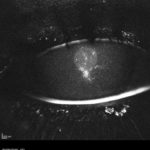

Cheratiti in portatore di lente a contatto